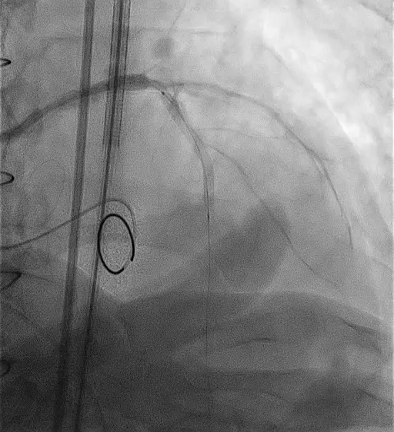

SEV 24mm. was deployed and during reheathing patient developed circulatory collapse.

SEV 24 mm was chosen based on CT measurement and bifemoral access was obtained. Carotid filter was placed for cerebral protection.During resheathing of the valve there was sudden circulatory collapse. CPR started and left coronary catheterisation revealed occlusion of left main. Flow was established in LAD with immediate wiring and ballooning. Finally TAVR valve was deployed after LAD flow was established.LCX flow was then resolved and LM bifurcation PCI was done using crush technique Patient was finally discharged in hemodynamically stable condition.